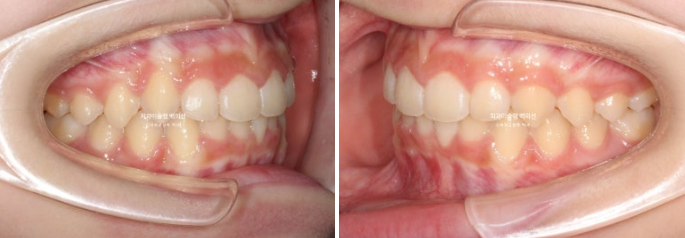

24년 2월부터 9월까지 장치를 모두 낀 후 모습입니다.

24.09

중심선이 아직 맞지는 않지만 과개교합이 해소가 되었습니다.

어금니 교합이 아직 완벽하진 않습니다.

배열은 좋습니다.

중심선, 교합 개선을 위해 추가장치 제작에 들어갔습니다